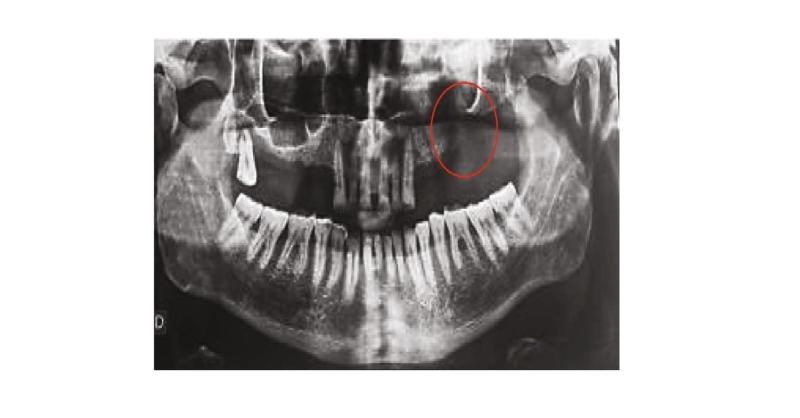

Mucoepidermoid carcinoma is a common salivary tumour with varying potential for aggressive behaviour. The morphological and spatial characteristics of the tumour, its extension to the neighbouring structures, the presence of metastases, the involvement of the lymph node, and the patient’s general condition determine the therapeutic choices (1). Her

Prosthetic Rehabilitation after Maxillectomy following Squamous Cell Carcinoma